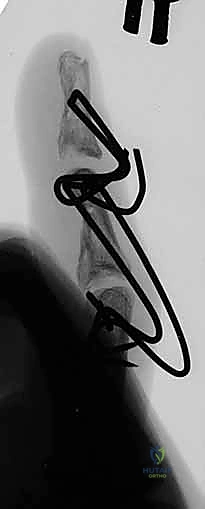

- Identify Distal Wire Level: Under image intensifier guidance, identify an appropriate level in the distal half to two-thirds of the middle phalanx. This placement must be distal to any fracture extension in the shaft of the middle phalanx to ensure adequate purchase in healthy bone. Mark this level on the skin.

> PEARL: For pilon fractures with significant distal extension, the distal wire can be placed as far distally as the head of the middle phalanx, or even near the center of rotation of the distal interphalangeal (DIP) joint. The middle phalanx is often narrowest proximally, so a more distal placement often provides a wider bone segment for easier and more secure wire placement. I have never encountered a fracture so distal that adequate fixation could not be achieved.

Figures 1D and 1E (TECH FIG 1D,E) illustrate finding and marking the position of the distal wire. Note how this placement is more distal than average, towards the head of the middle phalanx, due to an associated DIP joint injury, providing ample bone for fixation.

-

Initial Distal Wire Insertion: Similar to the proximal wire, insert the 1.1-mm K-wire percutaneously, aiming for the center of the middle phalanx. This wire must be perpendicular to the long axis of the finger and, crucially, parallel to both the plane of rotation of the PIP joint and the previously inserted proximal wire. This parallelism is essential for creating a functional dynamic construct.

Fluoroscopic Confirmation (Partial Insertion): Insert the wire partially through the middle phalanx and check its position carefully with both PA and lateral views on the image intensifier.

*Figures 1F and 1G (TECH FIG 1F,G) confirm the insertion and position of the distal wire on the image intens